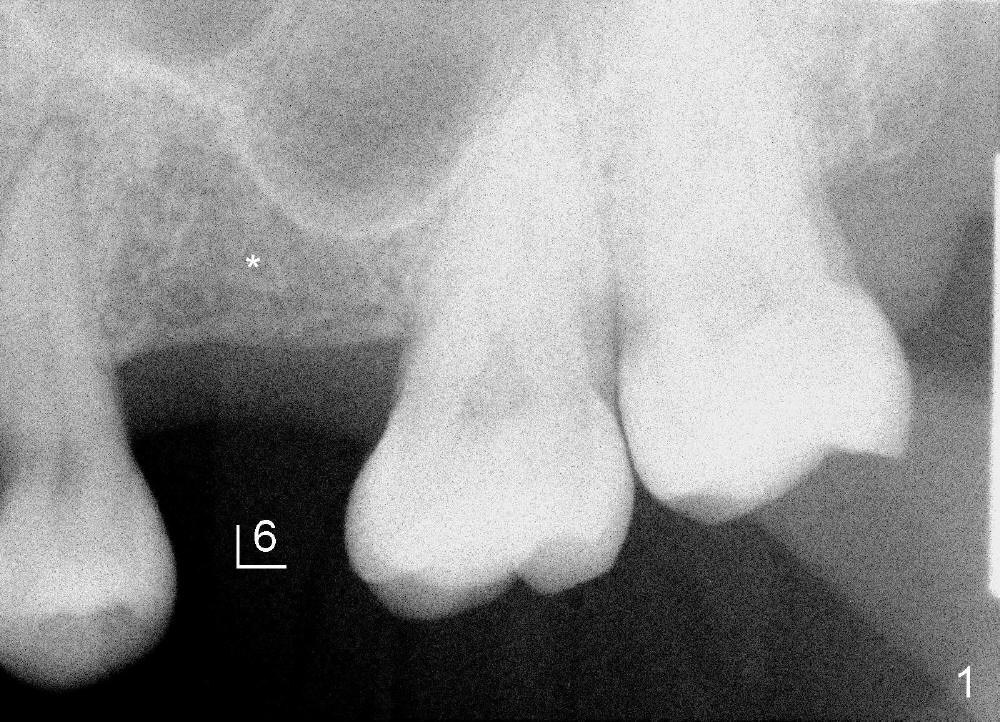

A 44-year-old lady has lost two of the 1st molars (upper left (Fig.1-3) and lower right (Fig.4-6)) for several years. Fig.1,4 are preop PAs, Fig.2,5 CT sagittal sections, and Fig.3,6 CT coronal sections. The adjacent teeth shift and tilt into the edentulous space.